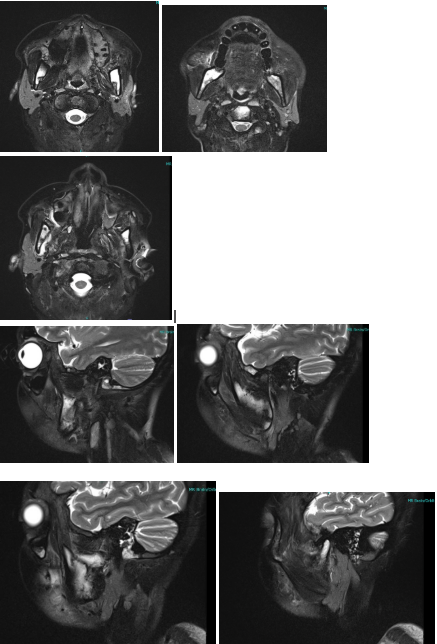

T2-weighted MRI Images for Case 1: Abnormal ill-defined hyperintense signals in the mandible